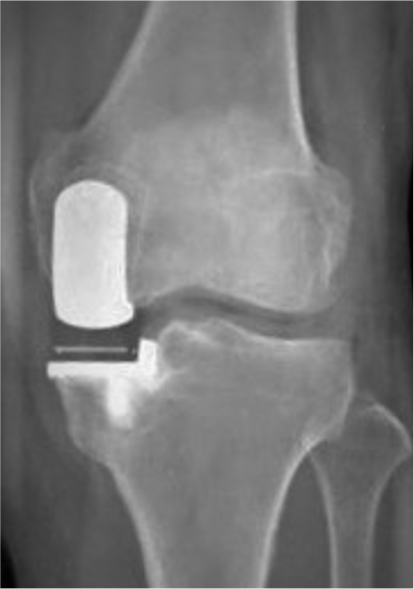

骨きり術の中でも、Opening Wedge法を採用しています。骨きり術とは、脛骨(すねの骨)の一部分に切れ目を入れて、間を広げ、O脚となっている脚を軽いX脚に矯正した状態でプレートで固定する手術です。体重のかかる軸を内側から外側に移動させることで痛みが取れ、また傷んだ軟骨も再生することが知られています。人工関節と異なり、“関節温存手術”と言われ、関節の機能が温存できる、低侵襲で合併症が少ない、良好な可動域(ひざを深く曲げることが可能)、スポーツなどに制限がない、などのメリットがあり若年者や比較的軟骨の残っている場合に行われます。 デメリットとしては、切った骨が治る(骨癒合)までに時間がかかり、リハビリ・社会復帰にやや時間を要することです。

HTOの術後レントゲン